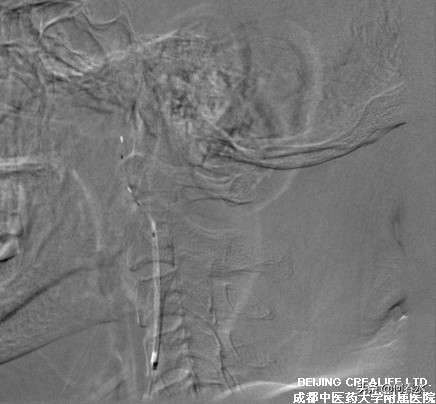

影像资料如下:

图片说明:在远端保护伞的情况下,送入支架